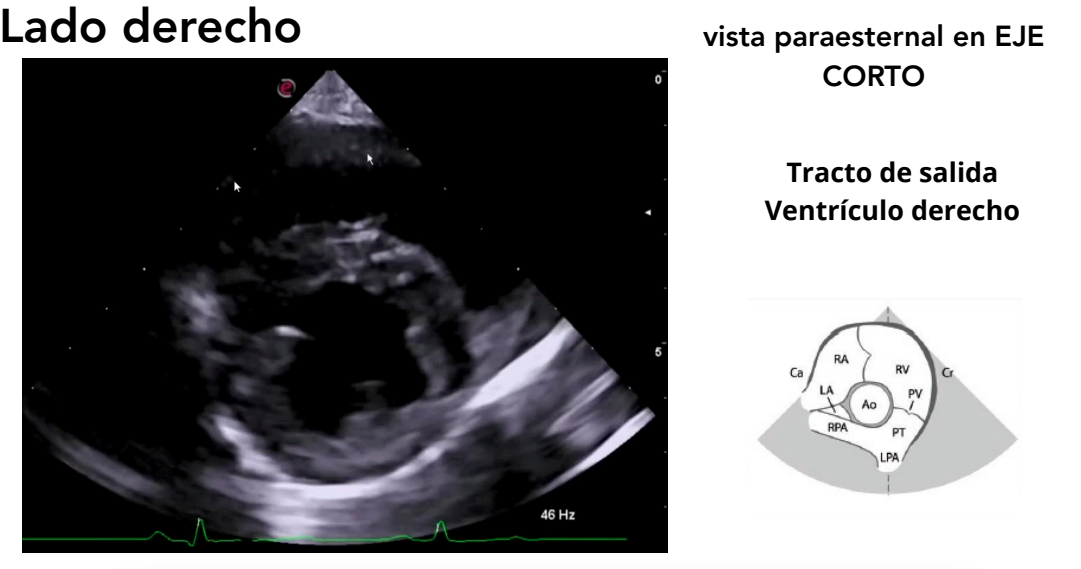

Vista paraesternal en eje corto

- Niveles observables:

- Tracto de salida del ventrículo derecho

Tracto de salida del ventriculo derecho

Modo M: se emplea para medir:

- Diámetro VI (sístole y diástole)

- Espesor del tabique IV (sístole y diástole)